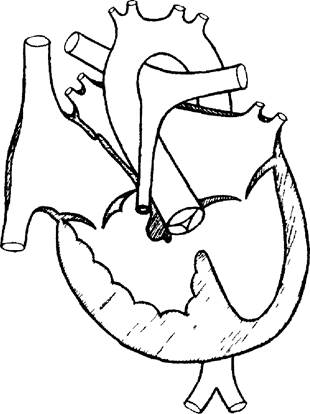

Рис. 4. Схема сердца с открытым артериальным протоком.

Рис. 5. Схема сердца с тетрадой Фалло.